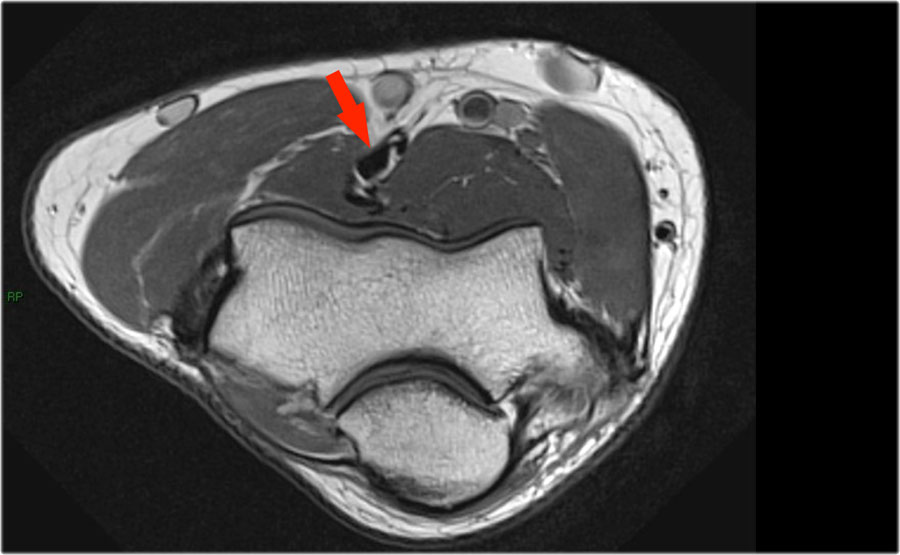

Cuộn qua các hình ảnh cắt ngang của gân cơ nhị đầu từ chỗ nối cơ-gân đến điểm bám tận trên lồi củ xương quay.

Bệnh lý của gân cơ nhị đầu đoạn xa rất giống với bệnh lý của gân Achilles.

Có thể gặp thoái hóa gân, rách một phần và rách hoàn toàn có hoặc không có sự co rút.